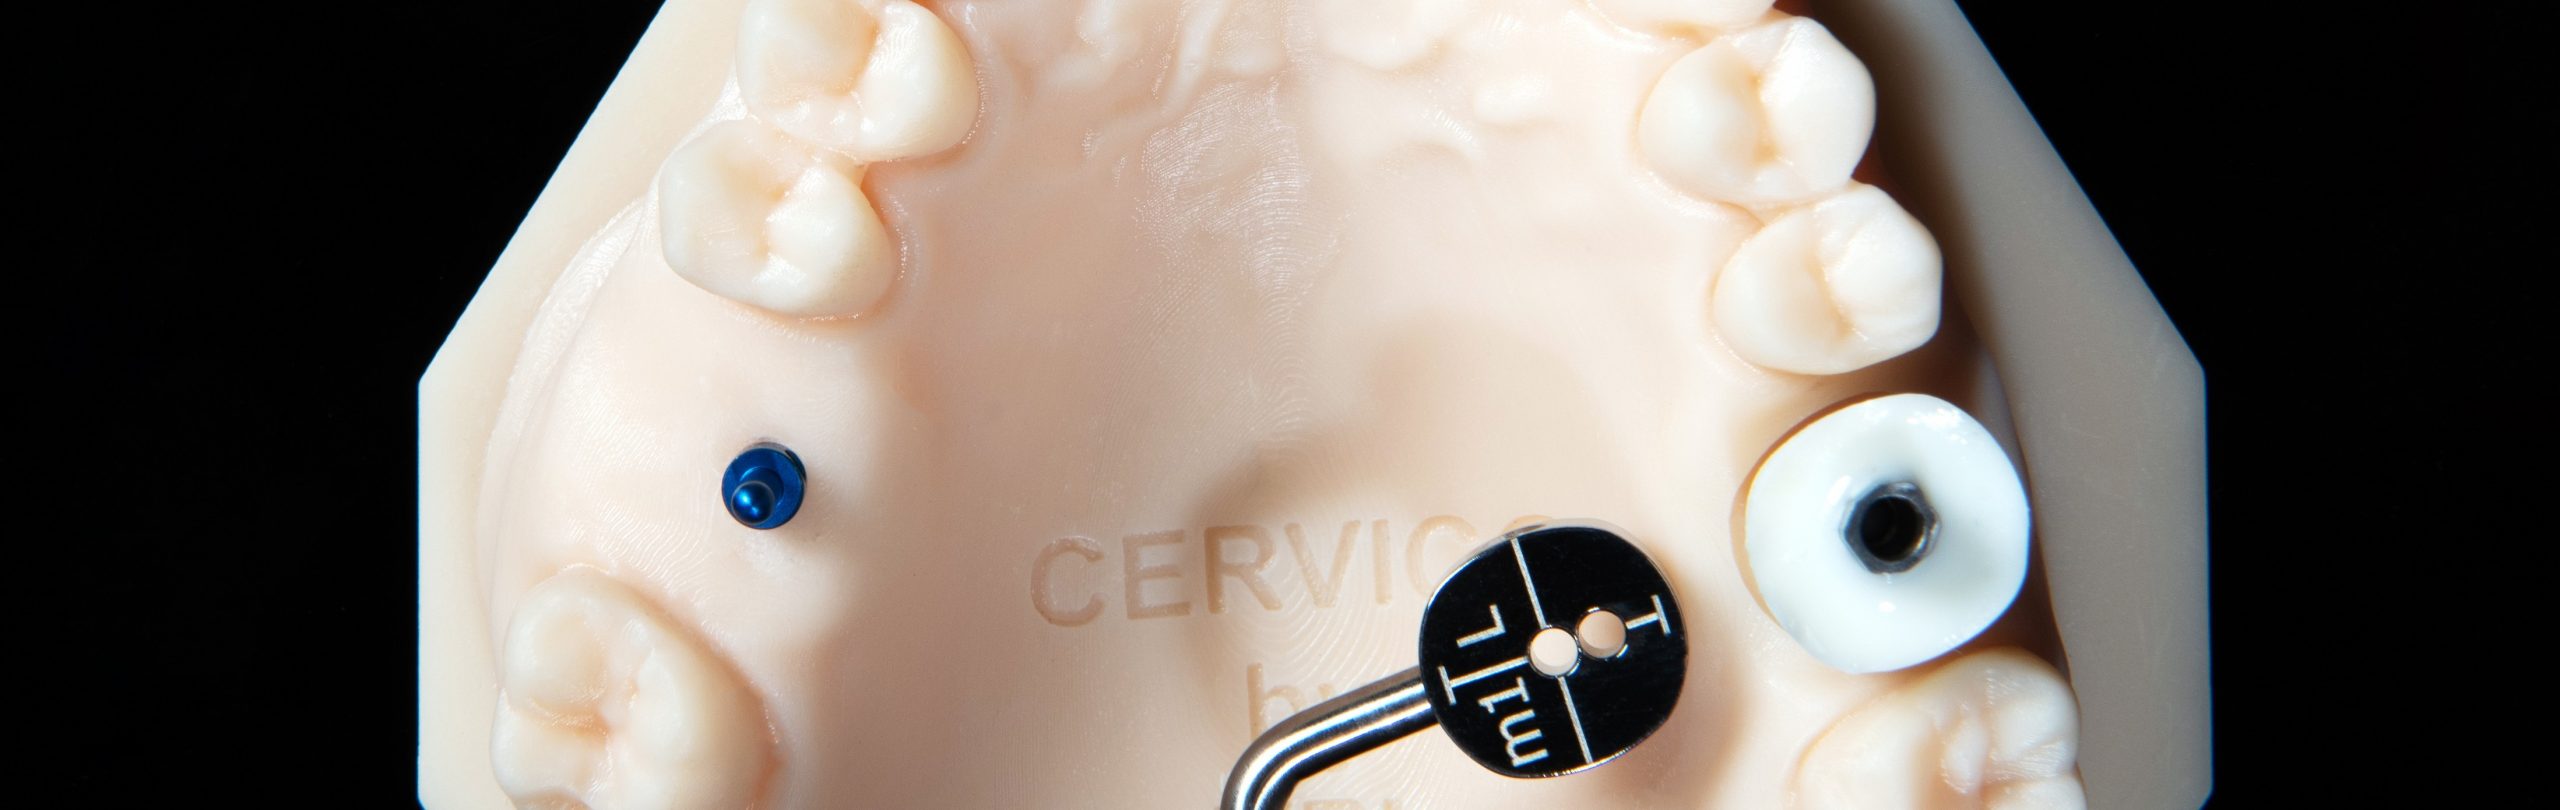

Pasul 3 – Identifică orientarea corectă a conexiunii protetice a implantului care urmează să fie plasat

Linia T imprimată pe fila formă anatomică îți oferă infor mații despre modul în care conexiunea protetică a implantului ar trebui să fie orientată în spațiu.

Acest lucru va asigura că bontul personalizat de vindecare va fi orientat în spațiu, odată cuplat la implant, cu aceeași orientare ca și cea descrisă de ghid.

Îți recomandăm să consulți documentul „Guide- Prosthetic connection orientation” de la acest link: https://bit.ly/2Sb0Mzx pentru informații detaliate despre orientarea corectă a conexiunii protetice pe marca implantului.

Asistentul instalează un bont temporar în puțul matriței cu codul corespunzător (E.g pS) la cel din fila de formă anatomică a ghidului (E.g pS).

Instalează bontul personalizat de vindecare în implant, utilizând șurubul de reținere disponibil împreună cu bontul temporar utilizat.

Instalează bontul personalizat de vindecare în implant, utilizând șurubul de reținere disponibil împreună cu bontul temporar utilizat.

Evaluează potrivirea clinică și radiografică adecvată cu implantul.